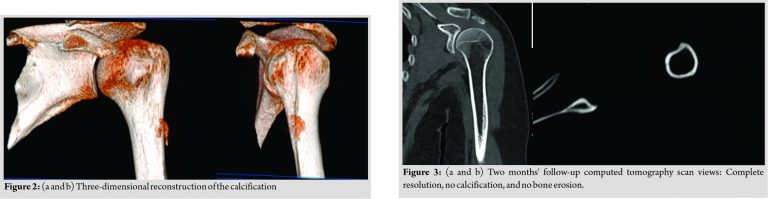

The calcification measured 4.2 cm in its longest axis with two radiological aspects common to calcifications: Comet tail sign and flame appearance (Fig. 2a and b).

A follow-up CT scan was performed 2 months after the beginning of symptoms. Complete resorption of calcification was observed (Fig. 3a and b). Cortical erosion had disappeared, without sequelae (Fig. 4a and b). On clinical examination, the patient was completely painless with complete active and passive shoulder range of motion. Forced adduction and internal rotation were painless. Palpation revealed no painful areas. Hyperparathyroidism management was done in coordination with an endocrinologist. At 1 year, there was no recurrence, shoulder mobility was complete and painless. Radiological control was without abnormality.